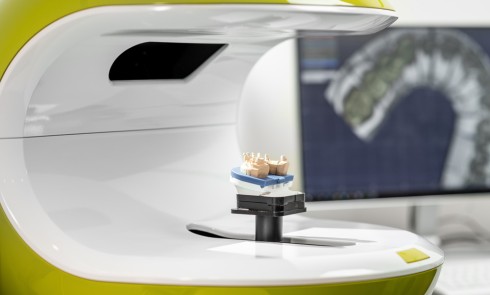

• la coulée des modèles est effectuée avec du plâtre dur (classe IV) sous vide ;

• après la prise du plâtre, la cire…